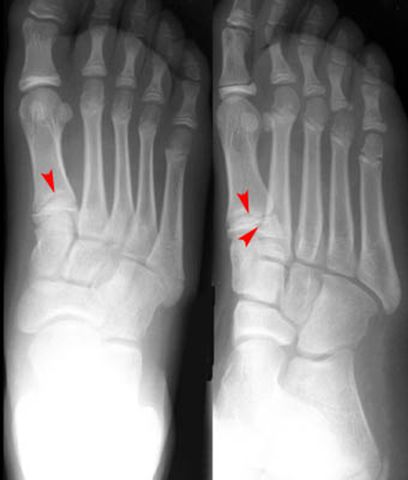

Jones Fracture

第五跖骨基底部骨折

易漏诊

不制动易致骨不连

跖骨骨折